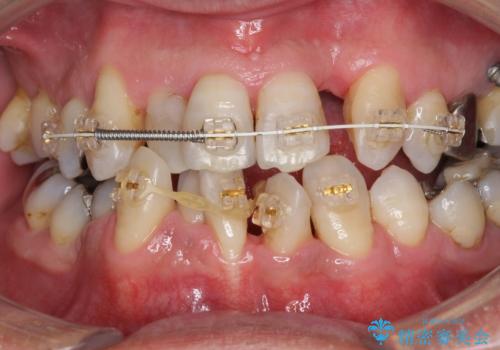

受け口 なんと部分矯正で治るんです!! インプラントを含めた総合歯科治療

- 歯周病を気にして来院。

前歯の虫歯を治そうにも、歯並びの問題で難しい状態でした。

右下の奥歯も欠損しており、インプラント治療が必要な状態でした。

前歯の部分矯正を行い受け口を改善しました。

奥歯まで動かそうとすると顎の手術の適応になってしまうため、奥歯はそのままにして前歯のかみ合わせを改善しました。

また、奥歯はインプラント治療を行い、矯正で下の前歯を後ろに下げるのに使用しています。

前歯が重なっているところの虫歯治療が難しく、そこから矯正治療の提案となりました。

下の前歯1本、また、左上2番を保存不可能なため抜歯しています。

通常骨格的な受け口を部分矯正でというのは不可能なことが多いのですが、今回はいろいろな条件が重ねなりお引き受け可能でした。通常は難しいです。